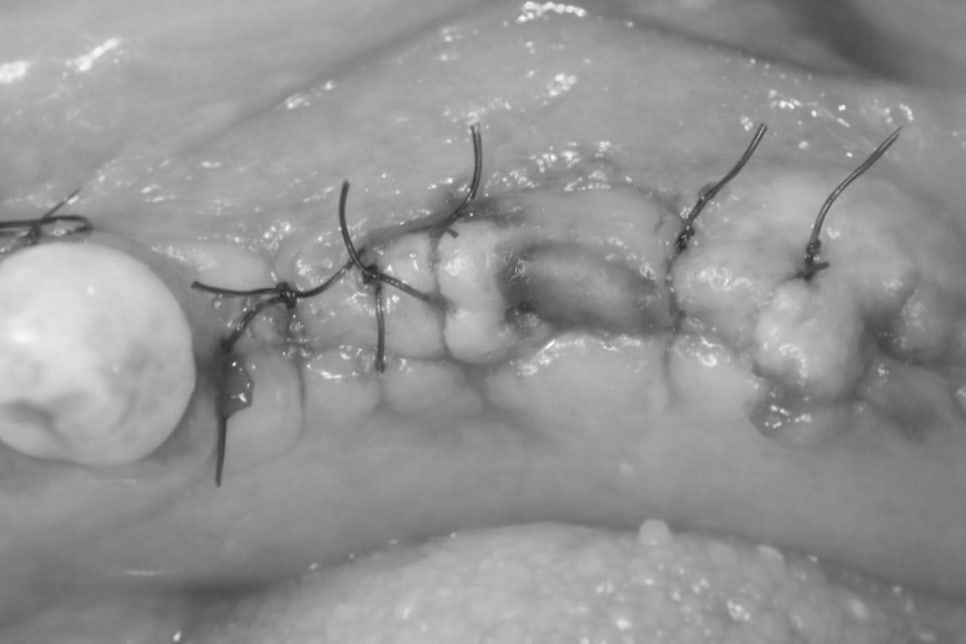

임플란트는 보통 잇몸을 절개하여

치조골을 노출시킨 뒤 픽스처를 식립하는

방식으로 진행되지만,

잇몸을 넓게 절개해 치조골을 노출시키는

기존 방식과는 달리,

잇몸을 열지 않고 픽스처를 심는 방법입니다.

치은을 크게 박리하지 않기 때문에

연조직 손상을 줄일 수 있으며

수술 후 발생할 수 있는 통증이나

부종의 부담을 낮출 수 있다는 특징이 있습니다.

또한 봉합 과정이 필요하지 않아

회복 과정 역시 비교적 빠르게 진행되는 편입니다.

절개와 봉합을 하지 않기 때문에

일상생활로의 복귀가 비교적 빠르며

임플란트 주변 잇몸의 형태를

보다 자연스럽게 유지할 수 있습니다.